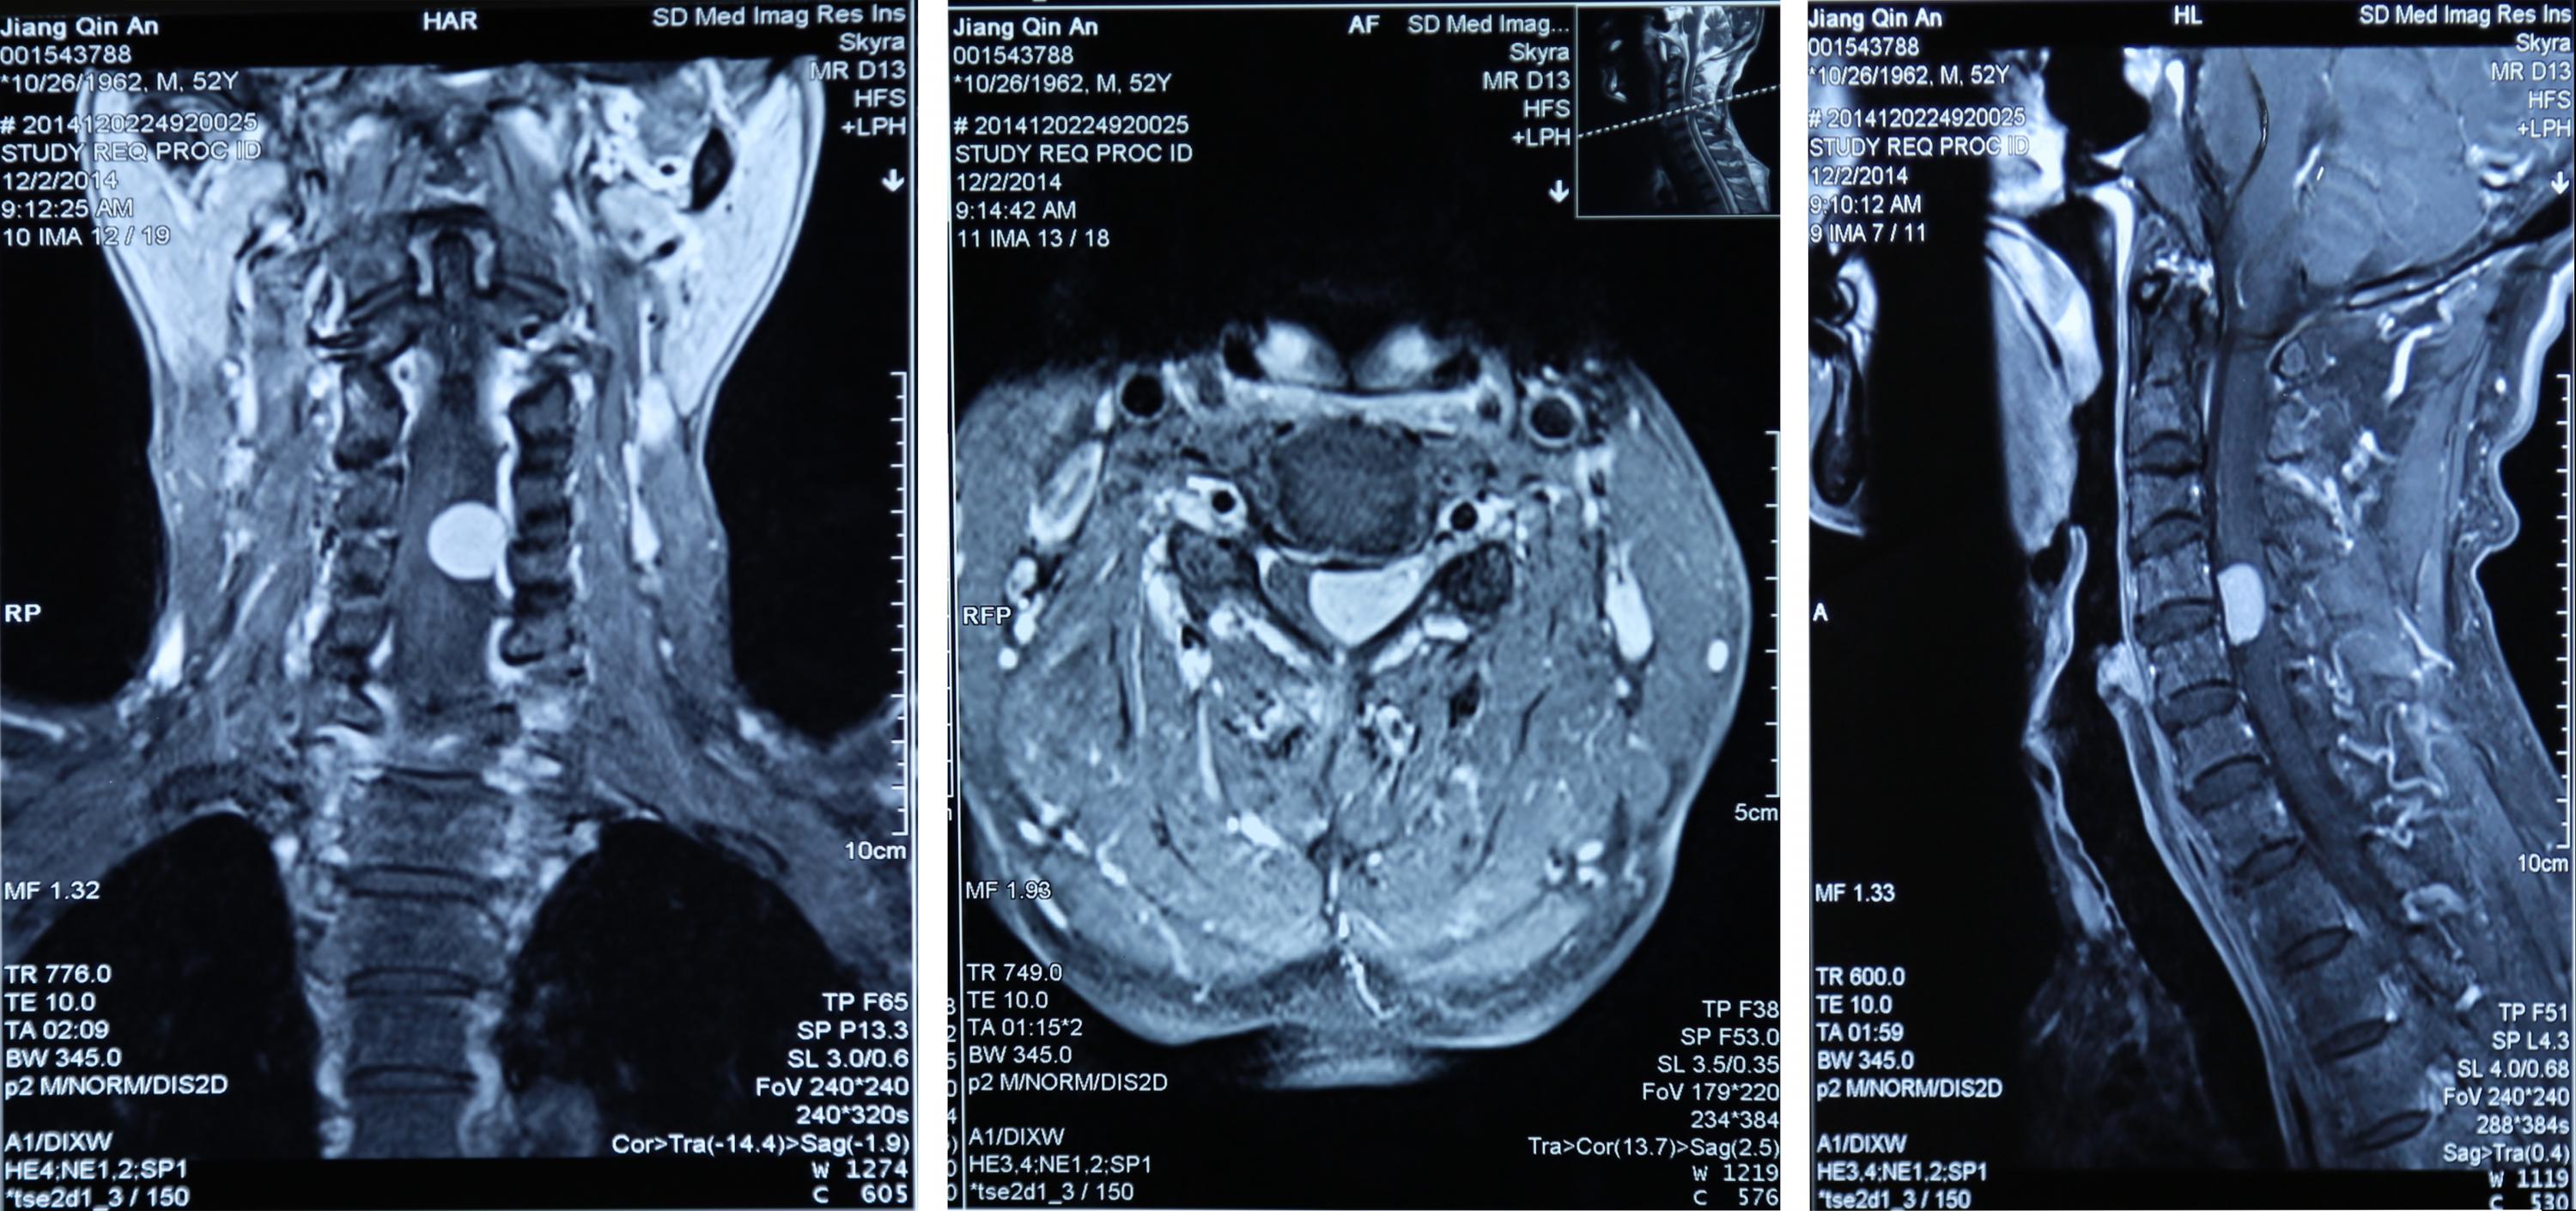

1月6日,李某慕名来到我院找副院长徐勤伟诊治,最终决定在市中医院接受手术。颈椎磁共振扫描显示:C4/5颈髓占位,肿瘤大小1.8×1.5×1.0cm。1月8日,李某在全麻下行颈髓肿瘤镜下全切除,手术历时6个小时。“麻醉醒了后我就感觉身上轻松了,手脚活动也灵便了。”李某说。

术 前 MR